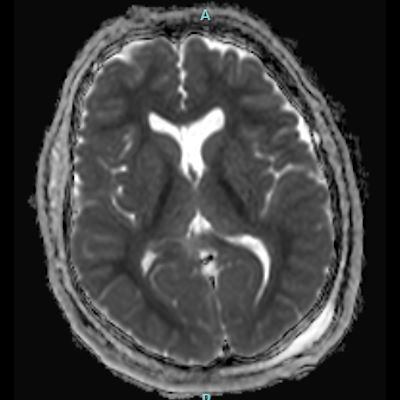

- A) Bilateral serebral kortekste (oklar) ve bazal ganglionlarda (oklar) yaygın DAG hiperintens, ADC hipointens difüzyon kısıtlamaları görülüyor.

- B) 9 gün sonraki difüzyon MR incelemede kortikal ve bazal ganglionlardaki difüzyon kısıtlamalarının gerilediği, bilateral serebral beyaz cevherde (oklar) ve internal kapsül arka bacağı- kortikospinal trakt boyunca (oklar) yaygın DAG hiperintens, ADC hipointens difüzyon kısıtlamalarının geliştiği izleniyor.

- T2A / FLAIR serilerde beyaz cevherde özellikle sentrum semiovalede diffüz yüksek sinyal görülür. Subkortikal U lifleri sıklıkla korunur.

- DAG görüntülemede sıklıkla belirgin difüzyon kısıtlaması görülür.

- Etkilenen beyaz cevher T1A görüntülerde sıklıkla hipointens olup kontrast madde verilmesi sonrası kontrastlanma görülmez. MR spektroskopide kolin ve laktat piklerinde artış ,NAA pikinde azalma görülür.